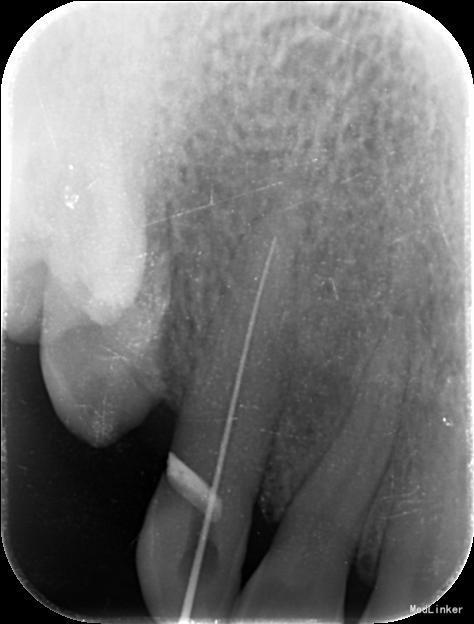

诊断:13慢性根尖周炎 治疗计划:13根管治疗后冠修复 治疗:1. 13去腐,腭侧开髓暴露髓腔,降牙合,探查根管,干燥根管,电测工作长度WL=25mm,此时根尖区探痛明显,按此长度插针拍片示超出根尖孔4mm,推算出WL=21mm。EDTA下,常规预备至35#,3%过氧化氢和生理盐水冲洗+超声荡洗根管交替进行。隔湿,干燥根管,封CP棉球, 氧化锌水门汀暂封。嘱勿用患牙咬物。 2.主诉:右上前牙上次治疗后后无不适。 检查:13暂封物在,叩痛(-),牙体无松动,牙龈未见明显异常。 处置:13去除暂封物,生理盐水冲洗并干燥根管,试尖到位,进口根充糊剂+牙胶尖冷侧压根管充填,氧化锌水门汀暂封,术后拍片示:13根充恰填。嘱勿用患牙咬物。 建议:13冠修复

根管治疗的关键是彻底清洁根管系统,对根管进行严密的充填,根管充填的止点是根尖狭窄处,即牙本骨质界,此处是解剖学和组织学牙髓末端及牙周组织的起始点,器械一旦超出牙本骨质界,就会对根尖周组织造成创伤,并将炎症带入根尖周组织。因此,在根管预备前,准确测定工作长度非常重要。 工作长度是指从牙尖至牙本骨质界之间的距离,它不同于牙的长度。 牙长度为切缘或牙尖至解剖根尖之间的距离。 临床上常用的方法有电测法、X 线辅助计算法,根尖定位仪借助于根管内部阻抗的规律性变化对其工作长度进行测量,准确性强,且应用简单方便,能够对根尖已经完成发育的牙根准确的测定其根管工作长度。但该方法亦具有一定局限性,如对戴有心脏起搏器患者严禁应用,同时期准确性也会因根管内外某些因素而受到干扰。X 线辅助测量通过将根管及根尖区域进行二维成像,在平面影像上确定根管长度,但这种平面影像只能分辨牙本质- 骨质界,而当根尖区不清晰时则无法准确判断根尖狭窄所在。同时这种方法测量准确性与拍摄技术、选用方法均有一定关系。 本病例先是通过根尖定位仪测量工作长度,但是在根尖定位仪显示至根尖狭窄时,长度为25mm,此时患者疼痛明显,按此长度摄插针X片,显示超出根尖孔4mm,推测出实际工作长度为21mm,按此长度预备后根管充填显示恰填。分析电测法出现误差的原因可能有两种,一是牙齿颈部的重度楔状缺损以及电解液的冲洗等可导致测量电流发生颈漏, 而使测量值不准确;二是由于根尖区牙槽骨受到破坏而导致骨小梁稀疏,锉尖在从根尖孔穿出后无法探及根尖处牙槽骨,而穿出一段距离后与根尖外部牙槽骨相接才形成回路,此时测量仪才会认为探及根尖而显示数值,故所得数值偏大。 目前, 根尖定位仪在临床应用上还是比较稳定的,在大多数的病例中定位根尖止点的准确性较高, 但是也会受到电解质、龈下龋、根折、根尖孔粗大和根尖未成形等因素的影响, 可能会产生错误结果,此时仍然需要X 线摄片的辅助。因此在使用根尖定位仪的过程中要注意, 当遇到一些特殊的情况时, 结合X 线照片法可以提高测量根管工作长度的准确性,此外,X 线片对牙体、牙周等组织情况均可以提供直观的影像,这对临床诊治具有十分重要的作用与意义。